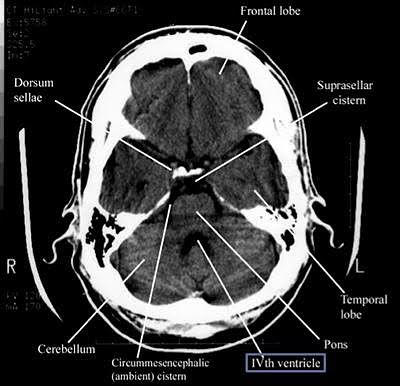

MRIs can help measure gray matter volume, thickness, and shape, and abnormalities have been documented with some of the most common mental health disorders like depression, ADHD, and anxiety.